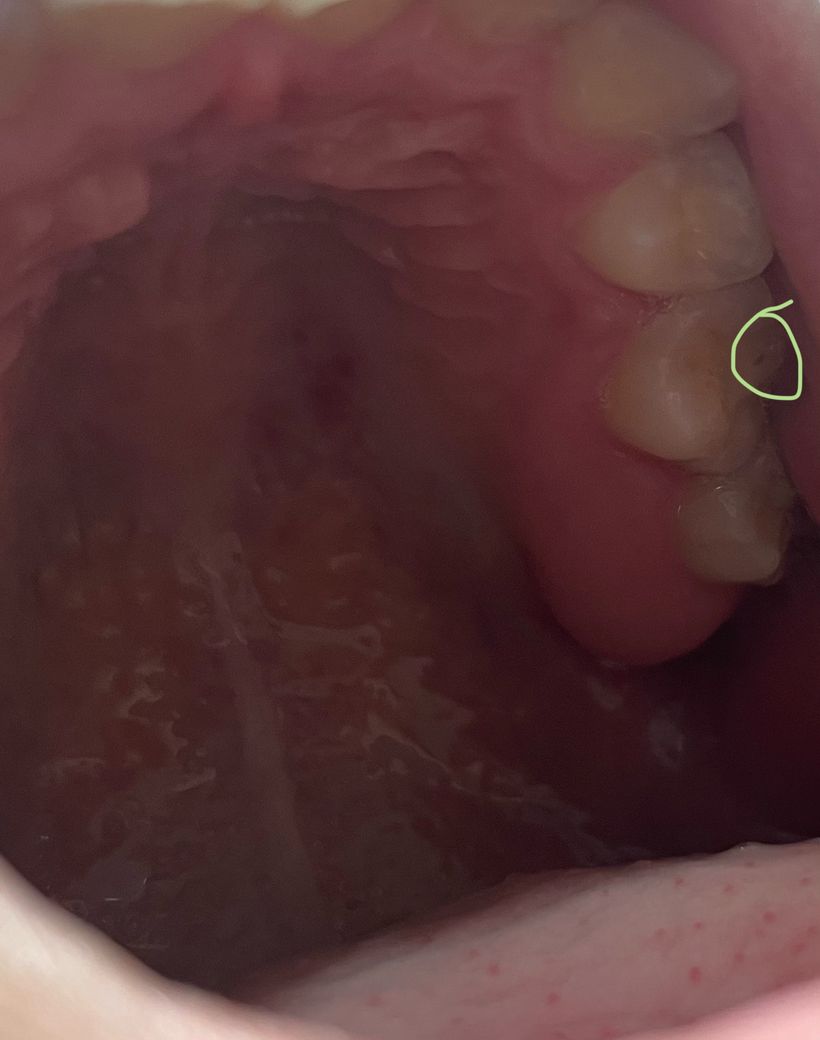

충치일까요?? 사진 첨부합니다 ㅜㅜ

동그라미 친 분이 충치일까 무섭네요... 인접면 보니까 레진 씌웠던 곳 같은데 빈 공간인지 충치인지 뭔지 모르겠어요... 아프거나 하진 않습니다 ㅜㅜ

사진이 흐려서 명확히 판별이 안되지만 충치로 보이진 않습니다.

크기가 커지거나 더 짙어진다면 치과에서 검사 받아보시는 게 좋겠습니다.

• 안녕하세요 치과의사 김철진입니다. 정확한건 치과에 가셔서 검진을 받아보셔야되겟지만 예전에 치료한곳이 떨어져 나간것처럼 보입니다.

• 촬영한 사진의 밝기가 너무 어둡기 때문에 충치의 여부를 확인하긴 힘들어 보입니다 치아의 검은색으로 보인다고 해도 충치가 아닌 단순한 착색의 경우도 있기 때문에 자세한 확인을 위해서는 치과에서 진료를 받아 보는 것이 좋습니다.

• 사진상 봤을때 충치의 가능성은 있어보입니다 다만 치료가 필요한 정도인지는 엑스레이사진을 찍어봐야 정확히 알 수 있을 것 같습니다